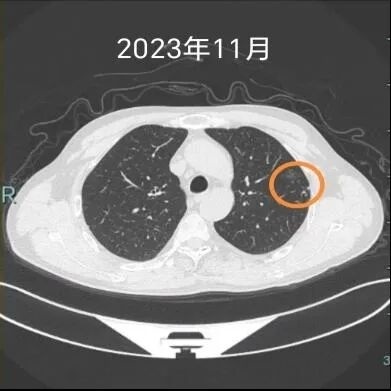

杨先生是一位有着三十多年烟龄的“老烟枪”,因为吸烟,手指头都被熏得焦黄。两年前,在一次单位体检中,他被发现左下肺有一个磨玻璃结节。经安徽理工大学第一附属医院医生诊断,考虑早期肺癌可能性大。

因为发现得早,医生建议手术治疗,所以杨先生很快就在该院接受了胸腔镜下亚肺叶切除术,手术非常成功。这次经历也让他痛定思痛、下定决心,把抽了半辈子的烟彻底戒掉了。